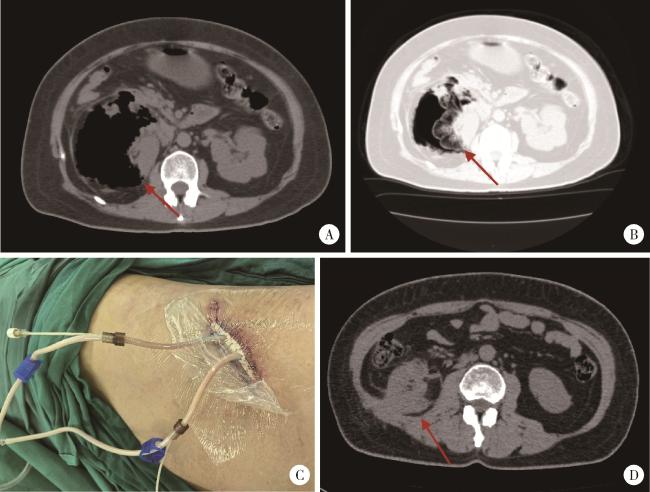

术后3个月随访结果:行保肾手术治疗的12例患者中有1例失访,余11例患者出院后3个月随访均无明显不适主诉,复查CT均无EPN复发,均无其他并发症发生,去掉单纯放置DJ管的患者2例(没有切口),余9例患者伤口愈合良好。图 2为1例典型EPN患者的术前CT平扫结果、VSD术后切口情况及出院前复查CT平扫结果。

图2 1例右肾EPN患者的术前、术后及出院前的临床资料,分级ⅢA级

Figure 2 Clinical data of a patient with right renal EPN at preoperative, postoperative, and pre-discharge stages, classified as grade ⅢA

A, preoperative abdominal window CT image showed extensive perirenal gas accumulation and complete disappearance of the kidney (red arrow); B, preoperative lung window CT image demonstrated the "vanished kidney" (red arrow) and massive intraparenchymal gas within the renal tissue; C, postoperative incision photo following VSD surgery; D, abdominal CT image prior to discharge revealed near-normal restoration of renal morphology, with no abscesses or gas in the renal parenchyma or perirenal region (red arrow). VSD, vacuum sealing drainage; EPN, emphysematous pyelonephritis.